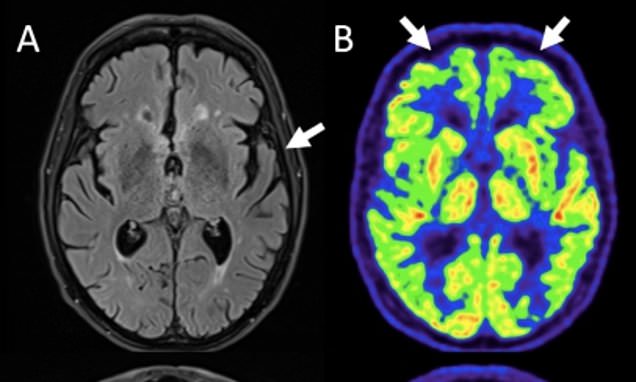

An 80-year-old man suffering from déjà vécu, a rare condition that causes a persistent false feeling that events are happening repeatedly, believed his Kindle was malfunctioning and giving him the same pages to read over and over again. MRI scans showed signs of Alzheimer's disease, which is the most common form of dementia that marks progressive and permanent cognitive decline. The patient's condition did not improve after treatment, and he continued showing signs of Alzheimer's for four years.